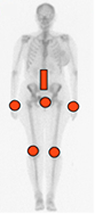

Fig 36. Distribución de la artropatía por cristales.

Compromiso simétrico, con afección de rodillas, muñecas, sínfisis púbica y columna.